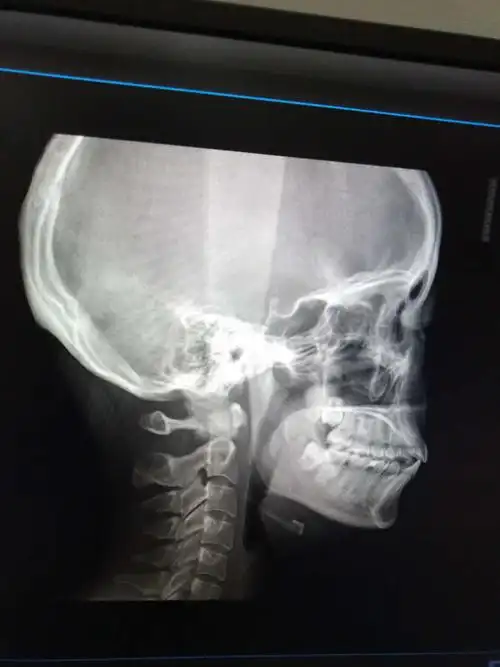

你好,我想问下我这个是骨性还是牙性,要是正畸可以改善嘴凸吗希望获得